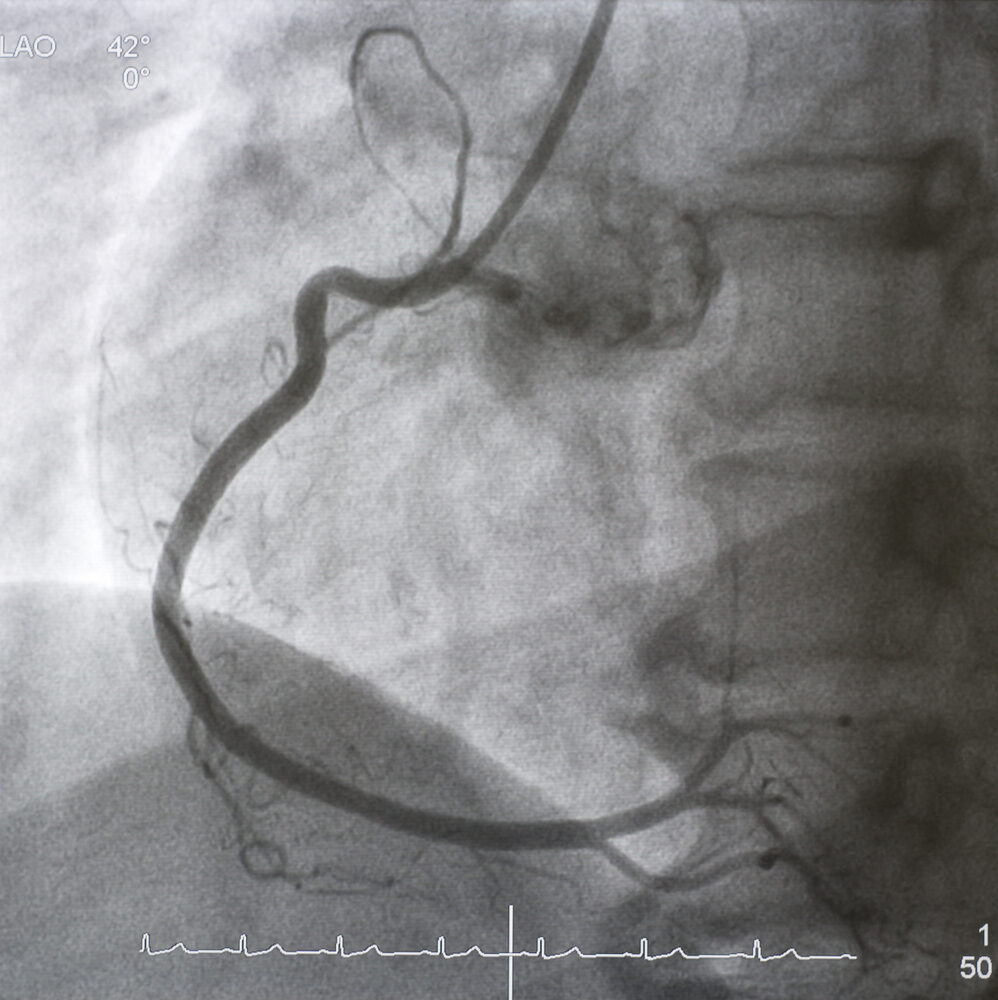

Untersuchung per Herzkatheter

Die Herzkatheteruntersuchung ist ein minimal-invasives Verfahren, bei dem ein dünner Schlauch (Katheter) über ein Blutgefäß zum Herzen geführt wird. Der Kardiologe nutzt diese Methode, um die Herzkranzgefäße zu untersuchen und Blockaden zu identifizieren.

Der Herzkatheter kann auch zur Behandlung genutzt werden. So ist es beispielsweise möglich, einen sogenannten Stents einzusetzen, der das Gefäß offen hält und so vor einem Herzinfarkt schützt.

Die Herzkatheteruntersuchung ist häufig bei der Diagnose schwerwiegender Herzkrankheiten und der Planung weiterer medizinischer Schritte entscheidend.

Die Herzkatheter-Untersuchung und die sofortige Behandlung spielen beim Herzinfarkt eine entscheidende Rolle. Es gilt, die Verstopfung im betroffenen Herzkranzgefäß zu beseitigen. Dazu kann der Arzt über den Herzkatheter einen kleinen Ballon in das Gefäß schieben und dieses damit weiten (sogenannte Ballon-Dilatation). Außerdem ist sowohl in der akuten Situation als auch zur Vorbeugung weiterer Herzinfarkte die Gabe von gerinnungshemmenden Medikamenten angezeigt.